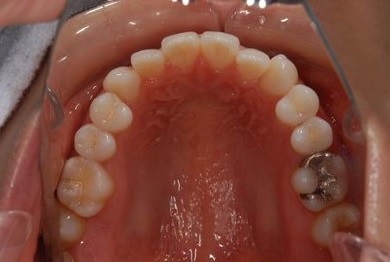

治療前

• 治療前